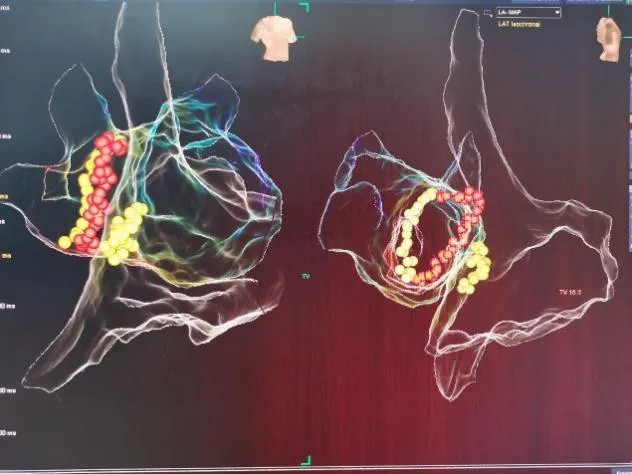

射频消融术

三维电生理系统支持下的房性心动过速射频消融术

三维电生理系统支持下的心房颤动+心房扑动射频消融术

长程持续性房颤射频消融术(环肺静脉隔离+顶部线消融)